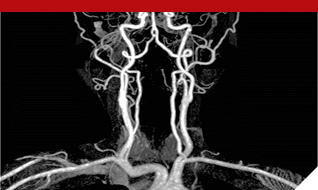

- 최신영상기술인 MRI와 CT, 핵의학에 대해 체계적으로 학습하며, 관련된 분야에 즉시 적용 가능하도록 교육을 실시합니다.

- 3차원영상처리 프로그램을 이용하여 영상을 만들어보고 영상해부학을 3차원으로 익히며, 미래의 IT 환경에 적응력을 높이고, 실무면접을 대비하는 교육을 실시합니다.